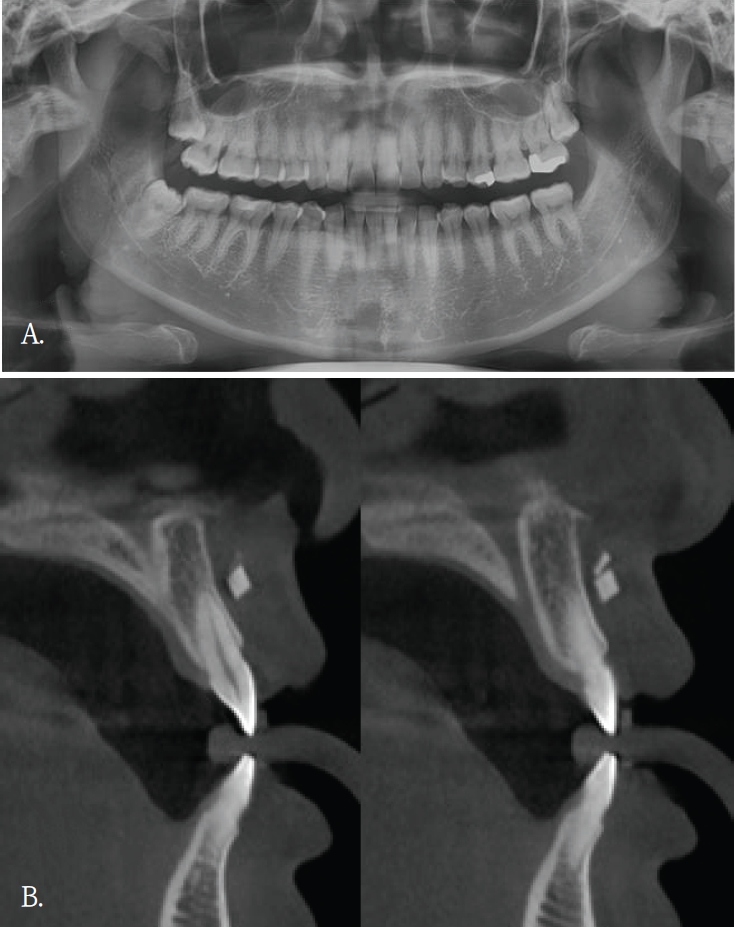

20대 여자환자가 윗 입술의 불편감을 주소로 내원하였다. 파노라마방사선영상에서 관련된 이상소견이나 병변이 관찰되지 않았다(Fig. 1A). 과거병력 청취에서 교통사고로 인한 윗 입술 열상의 봉합 병력이 있었음을 파악한 후, 외상 후 연조직 섬유화로 진단되었다. 1년 후, 이물감을 호소하면서 환자는 재내원하였다. 파노라마방사선영상에서는 여전히 이상소견이 관찰되지 않았기에, 콘빔CT검사를 시행하였다. 윗입술과 상악 전치사이 연조직부위에서 블럭모양의 방사선불투과성 이물질이 발견되었다(Fig. 1B). 이물질 제거를 위한 외과적 수술이 시행되었고, 술 후 해당 이물질은 유리조각임이 확인되었다.

증례 1에서도 초진시 파노라마영상에서는 유리조각을 관찰할 수 없었기에 연조직 병변으로 진단되었으나, 재내원후 촬영된 콘빔CT영상에서 연조직내에 있었던 이물질임으로 확인된 경우이다. 윗입술에 있었던 유리조각이 방사선불투과성 물질이였지만, 상악 전치부와 중첩되어 파노라마방사선영상에서 뚜렷하게 구분되지 않았다.

Fig. 1.

A. Panoramic radiograph shows no definite abnormality in the maxillary anterior region. B. Cross-sectional cone-beam computed tomographic image of the maxillary anterior alveolar region demonstrates a small block-shaped radiopaque foreign body in the labial soft tissue, without intraosseous involvement.